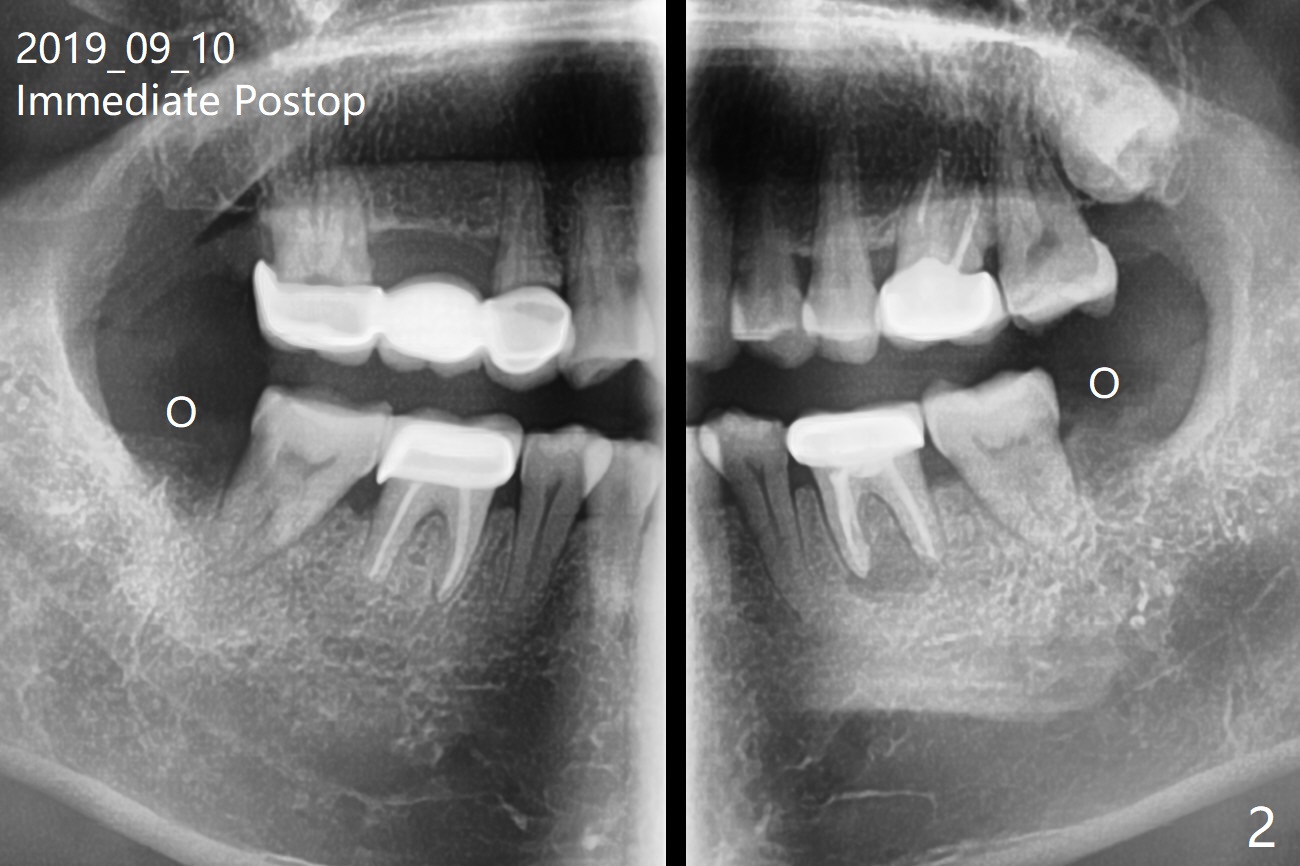

A 43-year-old man without significant medical history requests extraction of #17 and 32 (Fig.1). To prevent distal bone loss at #18 and 31, Osteogen plug is placed in the extraction sockets (Fig.2).